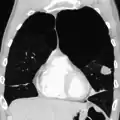

A CT scan is not routinely used except for the exclusion of bronchiectasis.[5] An analysis of arterial blood is used to determine the need for oxygen supplementation and assess for high levels of carbon dioxide in the blood; this is recommended in those with an FEV1 less than 35% predicted, those with a peripheral oxygen saturation less than 92% and those with symptoms of congestive heart failure.[111] WHO recommends that all those diagnosed with COPD be screened for alpha-1 antitrypsin deficiency.[42]

A severe case of bullous emphysema Axial CT image of the lung of a person with end-stage bullous emphysema

Axial CT image of the lung of a person with end-stage bullous emphysema Very severe emphysema with lung cancer on the left (CT scan)

Very severe emphysema with lung cancer on the left (CT scan)